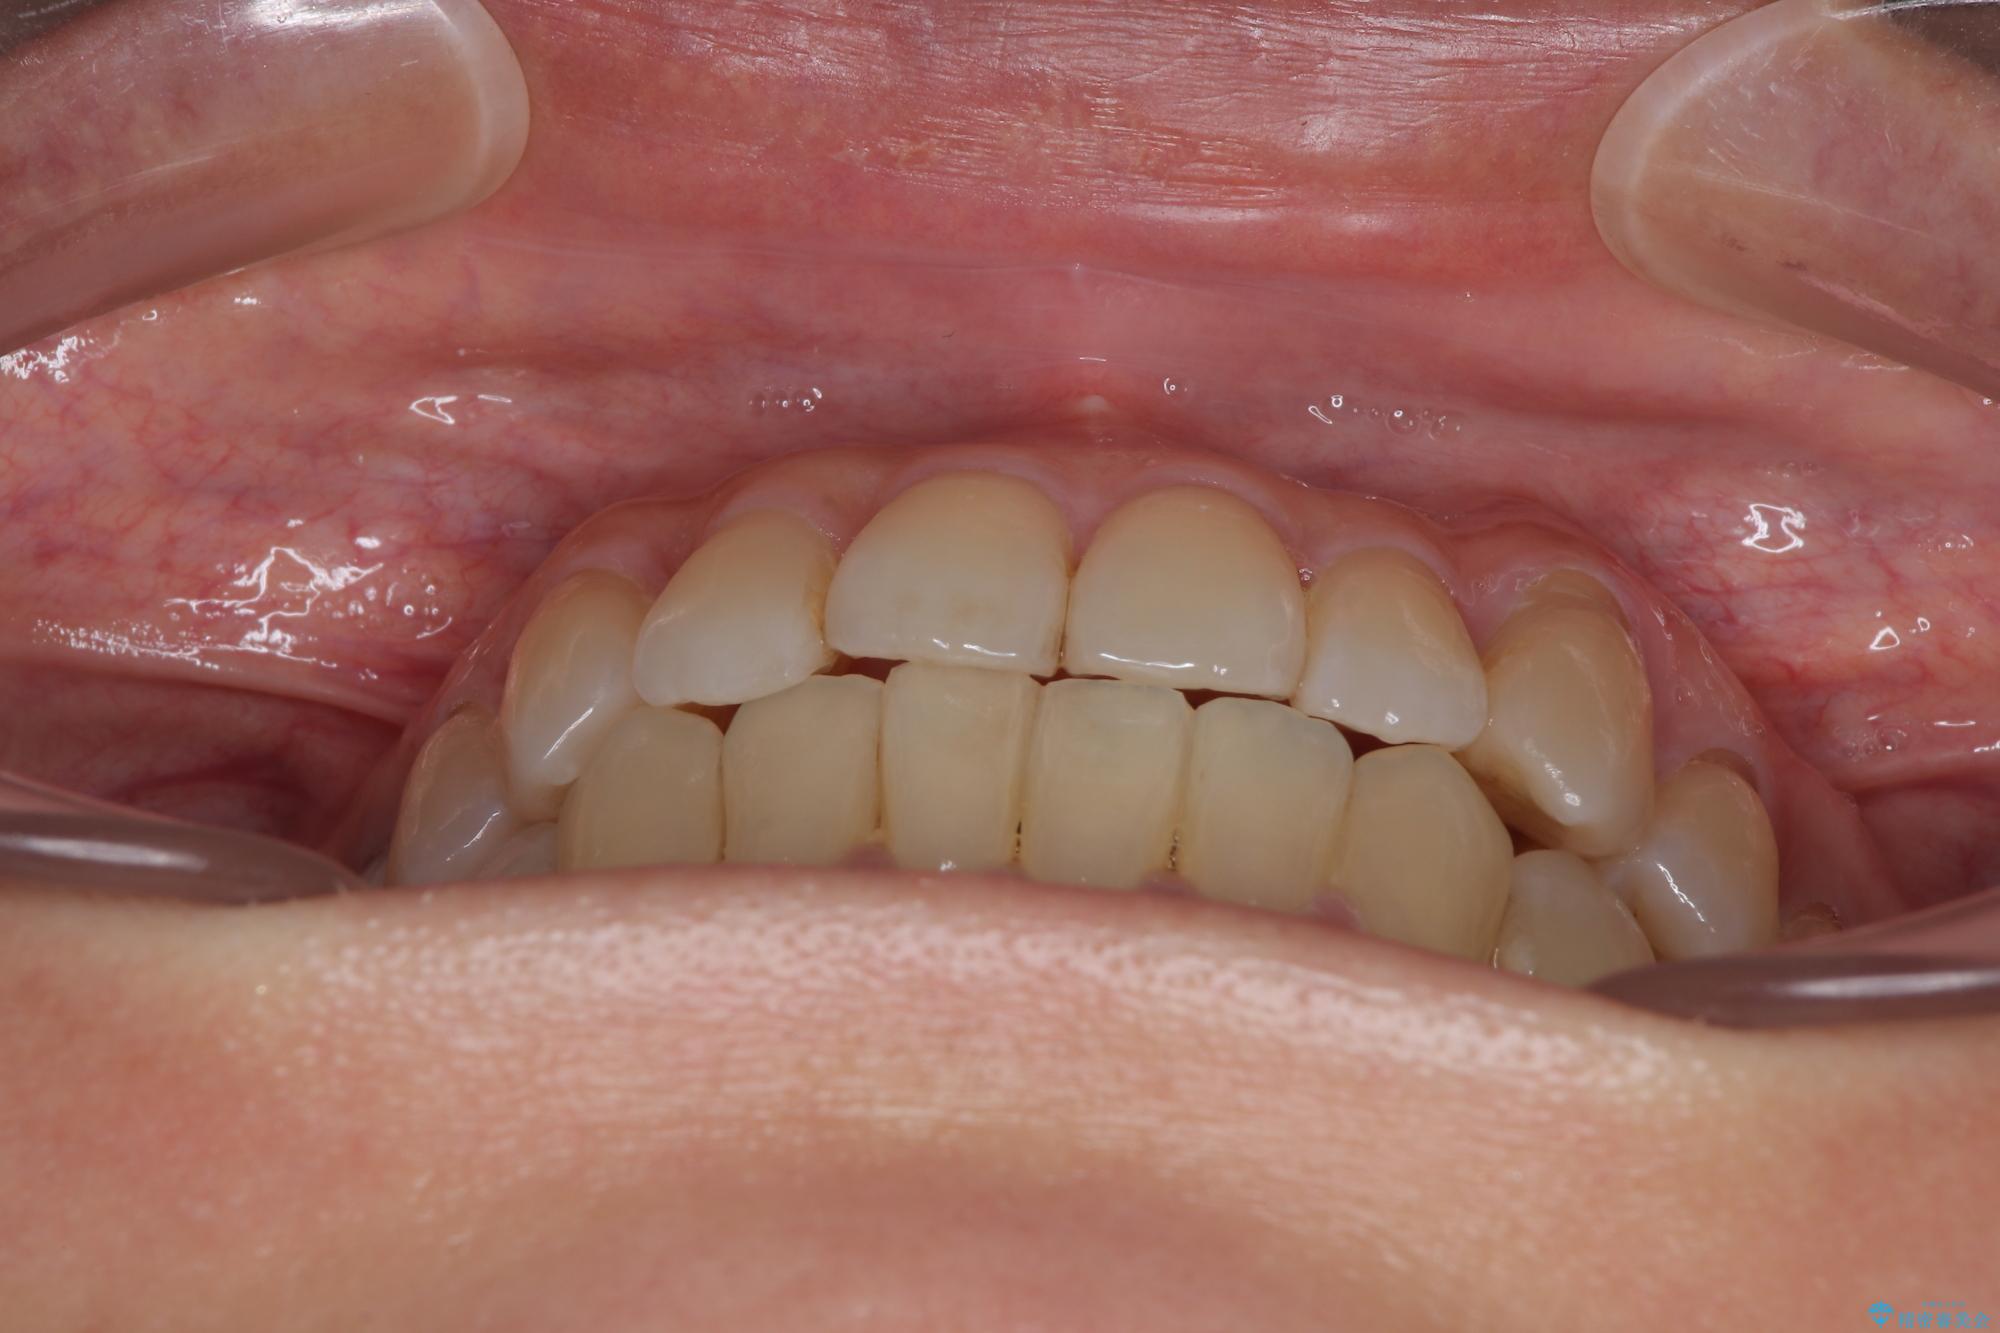

- 前歯のデコボコや八重歯を治したいとのことで来院された患者様です。

受け口傾向の骨格であり、前歯はクロスバイトまたは切端咬合となっており、下顎を中心に歯列全体の後方移動を行い、IPR(歯と歯の間を削る)によってデコボコが解消するように設計し、インビザラインにより治療を行うこととしました。

受け口傾向のインビザライン矯正は比較的治療を行いやすいため、きれいに仕上げることができました。舌の突出癖が顕著であったため、改善のためのトレーニングをしっかりと行っていただきました。